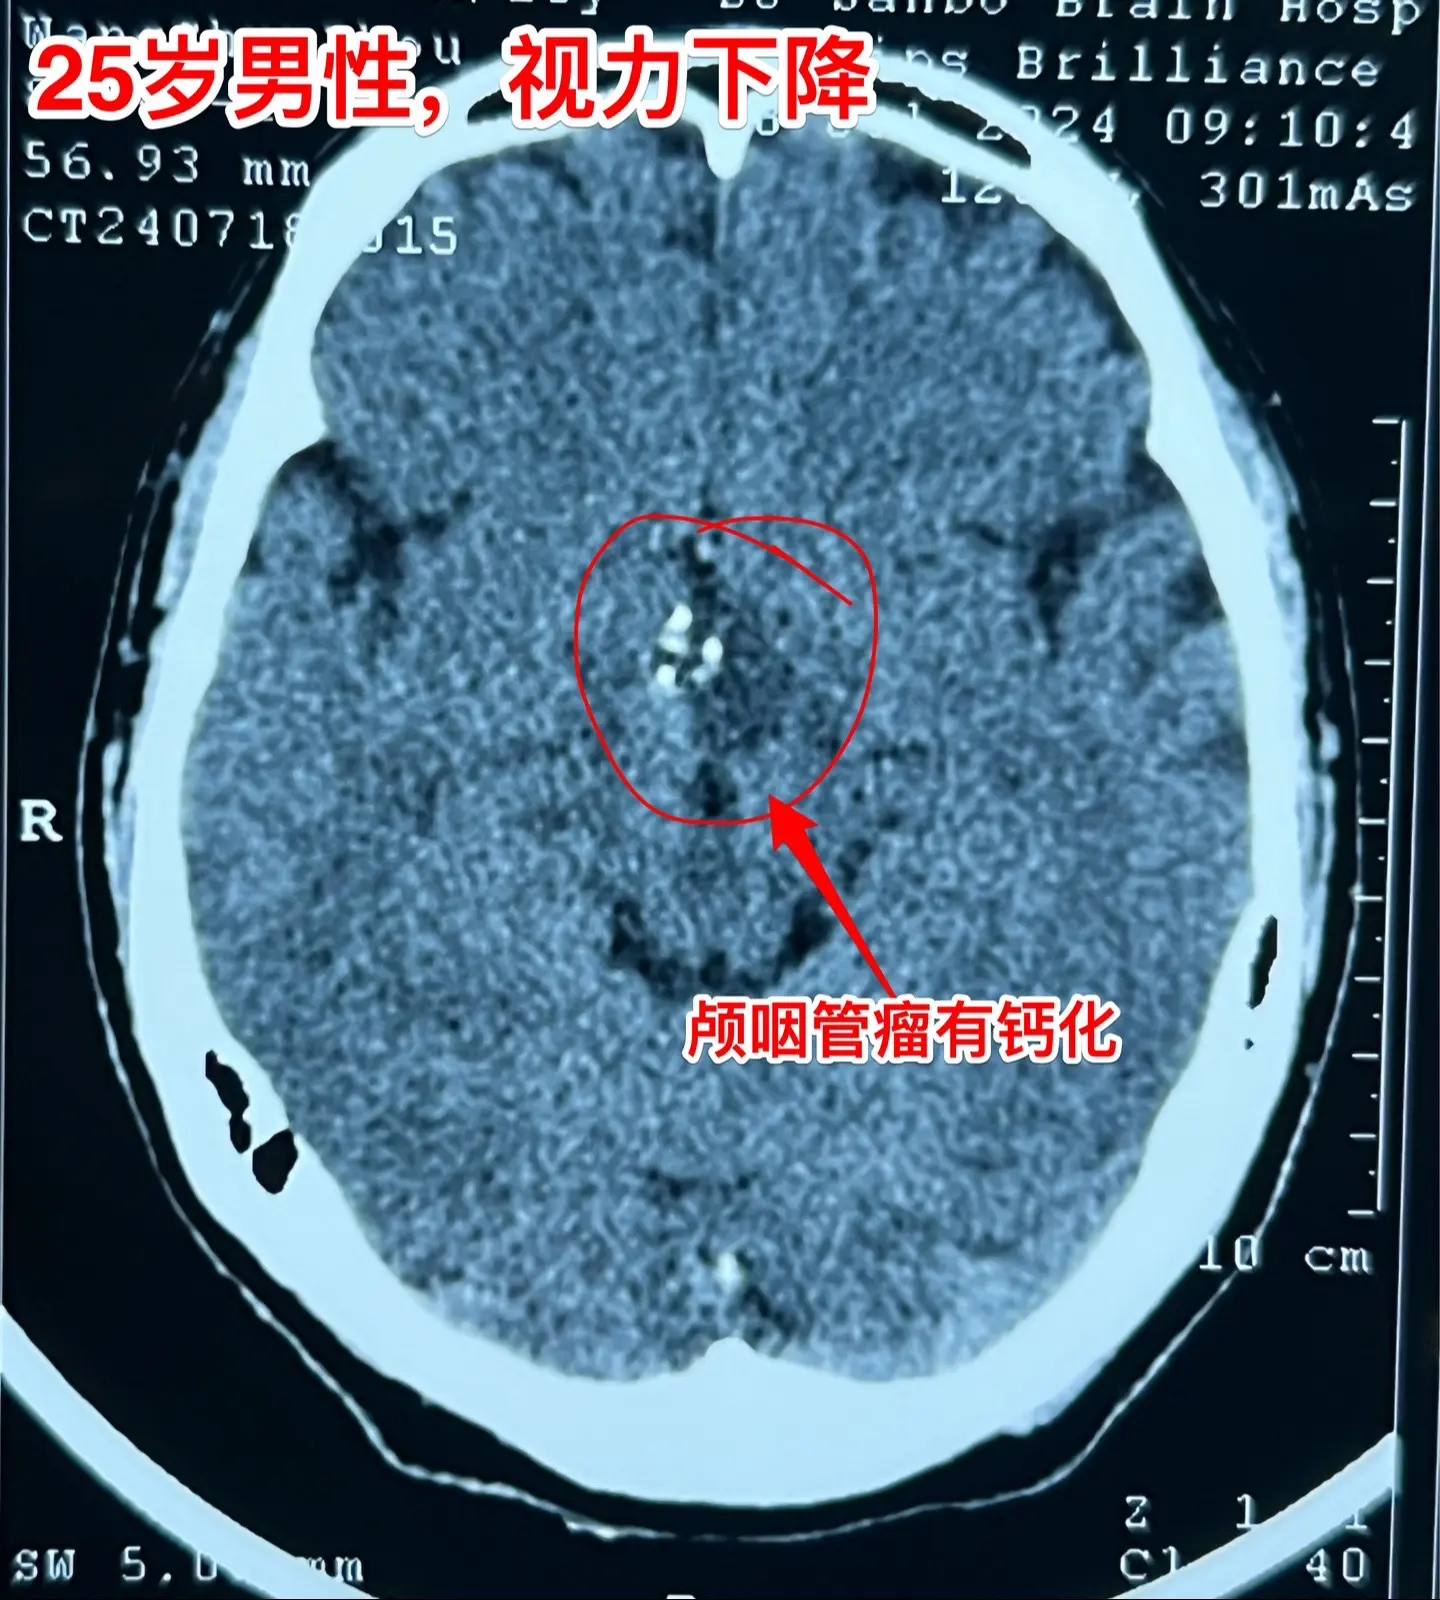

一天两台颅咽管瘤手术对于我们科是常态!7月24日我们科按常规安排了两台颅咽管瘤:第一个5岁男孩子,广东人,因为身高增长缓慢发现了颅咽管瘤。第二个是25岁的三门峡市男性,因为视力下降发现了颅咽管瘤。两个手术都顺利完成。 这样的手术安排对于我们三博脑科医院神经外科八病区来说几乎是常态。有时候一天完成两台复发颅咽管瘤手术,最多的时候一天完成三台颅咽管瘤手术。应该说如果一天只作一个颅咽管瘤手术是比较合理的,一天作两个劳动强度是很高的,不值得提倡。